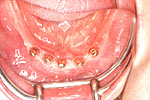

① 60才代の方です。まったく歯がありません。従来の総入れ歯を使用されていました。

食事でかむたびに入れ歯が動き、長い間不自由さを感じていました。上あごは長い間の入れ歯だった為、骨の厚みがなくなってインプラントは不可能でした。下あごの骨の厚みは可能な状態でした。

② 下あごにインプラント(人工歯根)を埋入しました。これで、まったく歯がなかったところに歯の土台が固定されました。

ここに、人工の歯を乗せしっかりと固定します。従来の入れ歯は歯がまったくない場合、歯肉に乗せるしかありませんでした。

③ 下あごの人工歯です。インプラントの上にキャップを入れてあります。

④ 従来の入れ歯のように見えますが、大きな違いは中央の黒く見える部分(実際は銀色)を上図の埋入したインプラント (人工歯根)に乗せしっかりと固定します。これが動かない理由です。

⑤ インプラントの上に取り外し式の入れ歯が入りました。

⑥ インプラントが土台の下の総入れ歯が入りました。

60才代 女性 5本埋入

総額:225万円(税別)

治療期間:6ヵ月

リスク副作用:一時的な食事制限によるQOLの低下。腫脹。神経障害。出血。咬合歯の負担増加。